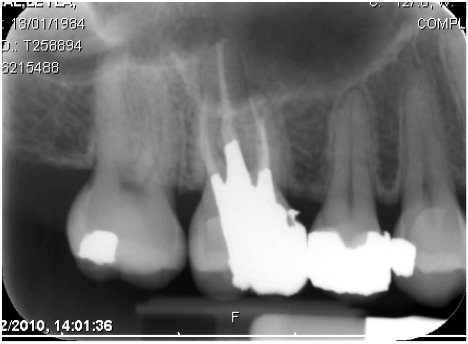

الضرس بعد التحضير

خلصت دراسة الى أفضلية عمل تلبيس Crown للاضراس المعالجة لبيا. كما انه لاضرورة لاستخدام الاوتاد الداعمة للأضراس التي تم علاجها لبيا اذا كان طول التاج بعد التحضير من3 الى 4 ملمRosenstiel, Contemporary Fixed) .(Prosthodontics,4th Ed, 2006